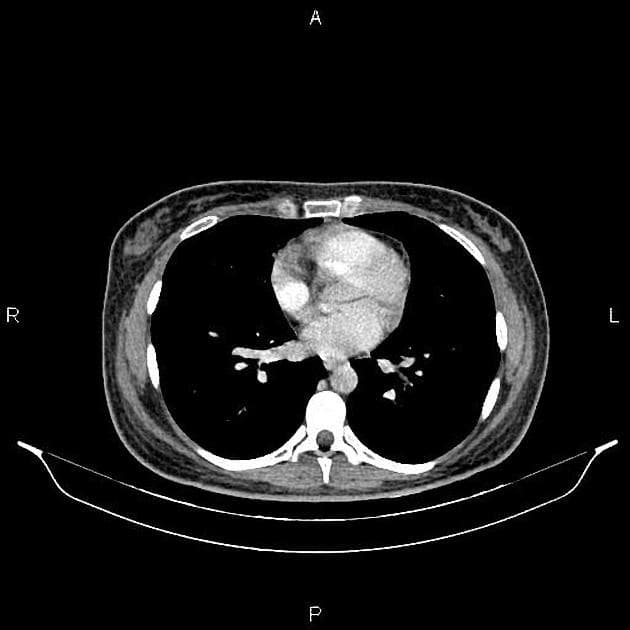

- Tổn thương dạng thùy (lobulated) kích thước 35 x 45 mm nằm ở phân đoạn V của thuỳ phải, liền kề với túi mật (gallbladder).

- Tổn thương này tăng tín hiệu (hyperintense) trên hình ảnh T2-weighted MRI.

- Trên hình ảnh cộng hưởng từ có tiêm thuốc tương phản động (dynamic contrast-enhanced imaging), thấy tăng quang dạng nốt (nodular) ở vùng ngoài viền (peripheral) ban đầu, tiếp theo là quá trình lấp đầy dần từ ngoài vào trong (slow centripetal filling).

Hình ảnh cộng hưởng từ (MRI) phù hợp điển hình với u sợi mạch gan (hepatic hemangioma).

- "U sợi mạch gan thường biểu hiện tăng tín hiệu T2 và tăng quang dạng nốt ở viền ngoài với quá trình lấp đầy từ từ từ ngoài vào trong trên cộng hưởng từ có tiêm thuốc tương phản động."

U sợi mạch gan là khối u gan lành tính phổ biến nhất, thường được phát hiện tình cờ trên hình ảnh học. Bệnh xuất phát từ các mạch máu bất thường và gồm các khoang giãn chứa đầy máu được lót bởi tế bào nội mô. Trên cộng hưởng từ (MRI), hình ảnh điển hình bao gồm tăng tín hiệu rõ rệt trên T2 và kiểu tăng quang dạng nốt ở vùng ngoại vi trong thì động mạch, tiếp theo là quá trình lấp đầy dần từ ngoài vào trong ở các thì muộn. Dấu ấn hình ảnh này rất đặc hiệu, cho phép chẩn đoán chắc chắn không xâm lấn trong hầu hết các trường hợp. Mặc dù có thể sinh thiết, nhưng thủ thuật này tiềm ẩn nguy cơ chảy máu và thường được tránh. Điều trị mang tính bảo tồn, không cần cắt bỏ hay theo dõi định kỳ trong các trường hợp điển hình, trừ khi có nghi ngờ chẩn đoán hoặc bệnh nhân có triệu chứng.